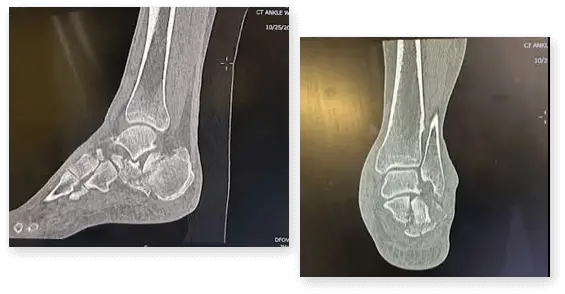

This story revolves around a woman who experienced a significant calcaneal fracture following a fall from a ladder. Dr. Ledesma's patient boasts remarkable achievements as an equestrian, poised to participate in the forthcoming world championship event scheduled for December 1st, 2023, a mere four weeks post-surgery. Given the specific requirements of her sport, necessitating non-weight bearing, Dr. Ledesma advised that successful surgery coupled with the application of a protective boot could potentially enable her participation. Below are preliminary images depicting the extent of her injury prior to the operation.

Dr. Ledesma observed that the level of fracture of the calcaneus was far from simple, evident from the accompanying pictures. Despite the complexity, Dr. Ledesma harbored confidence in piecing together the fragments, albeit with reservations regarding the stability of the repair within the limited timeframe of four weeks before the patient's event. This prompted consideration of techniques to expedite the healing process, leading to the consideration of Ossio.